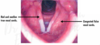

Diagnose? Symptomer: FAST * F: Fjes – facialisparese (hængende mundvig, asymmetri i ansigtet) * A: Arm – parese/-paralyse (nedsat kraft eller lammelse i arm) * S: Sprog – motorisk/sensorisk afasi (kan ikke tale eller forstå tale) * T: Tale – dysartri (sløret eller utydelig tale)

Apopleksi (stroke) og TCI (transitorisk cerebral iskæmi)